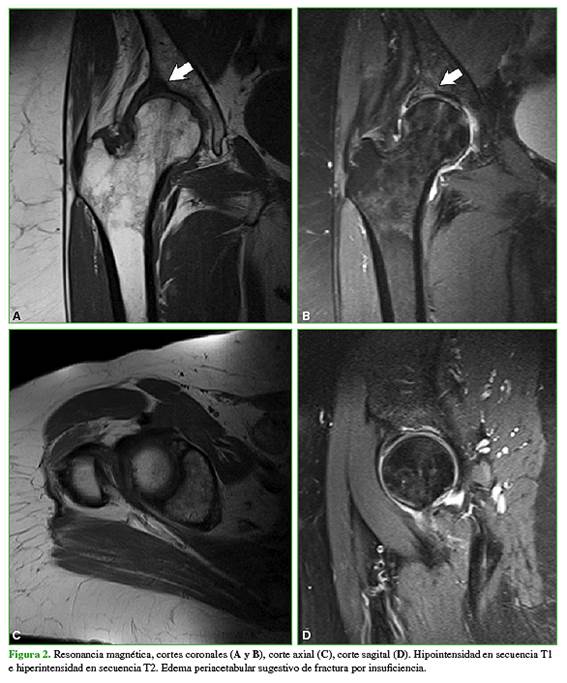

En las radiografías anteroposteriores y de perfil de ambas caderas, se observó un ángulo cervicodiafisario de 131˚, con un índice acetabular y un ángulo centro de borde lateral de Wiberg dentro de los límites normales en ambas caderas. En la cadera derecha, se observaron signos evidentes de desgaste articular con un estrechamiento de la luz articular y esclerosis subcondral, clasificada como grado 2 de Tönnis. Observando con mayor detenimiento, se detectó un escalón articular acetabular a nivel posterosuperior (Figura 1). Se solicitó una resonancia magnética (RM) cuyas imágenes revelaron una zona de hiperintensidad en el área de carga del acetábulo, lo que confirmó la lesión (Figura 2). Los parámetros bioquímicos no mostraron alteraciones significativas.